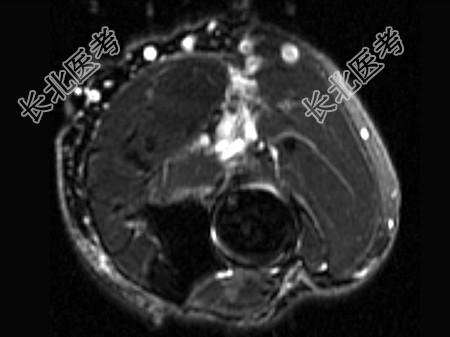

- 单项选择题女,44岁, 有外伤史,上臂远端疼痛, 结合图像,最可能的诊断是 ( )

D、肱二头肌腱远侧局部裂伤